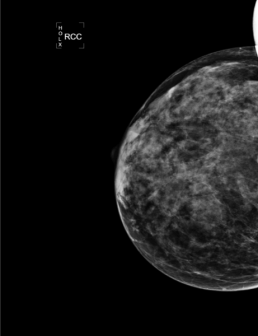

Cas de la semaine (semaine 32, 2022)

femme de 43 ans; palpation d’un nodule du sein gauche.

Mammoscreen™ pointe une opacité rétro mamelonnaire gauche associée à un foyer de microcalcifications poussiéreuses scoré à 9/10.

La biopsie mammaire confirme un adénocarcinome infiltrant SBR 2, RH+ HER2-, Ki67 à 15%.